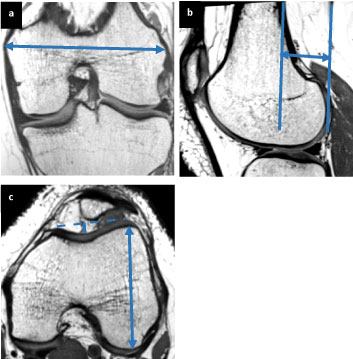

Morphology of the distal femur: This group of studies had the largest volume of articles and metrics investigated. Examples of distal femur metrics studied are seen in Figure 3. In nearly all femoral size metrics (including metrics such as epicondylar width, AP diameter of each condyle, height of the condyles, surface area of the distal femur etc.), males had greater unadjusted values. For example, unadjusted measurements of the AP dimensions of the medial condyle ranged from 55-64 mm in females with significantly greater dimensions in males in most papers, ranging from 61-70 mm [13-18]. Unadjusted AP measurements of the lateral condyle were also greater in males, ranging from 58-66 mm in females compared with 65-72 mm in males [13-17]. However, when adjustments for height, weight, femoral length, leg length, etc., were performed, many of these sex differences decreased or disappeared, or disagreement existed within the investigations. For example, one study showed statistically greater mean AP medial femoral condyle measurements in females (77 mm compared to 74 mm) and greater mean AP lateral femoral condyle measurements in males (79 mm compared to 74 mm) when normalized to the transepicondylar width of the femur [19]. Condylar aspect ratios were also controversial, with some studies showing no sex difference, some showing greater aspect ratios in males, and some showing greater aspect ratios in females. Studies also looked specifically at the intercondylar notch and found that while males have greater unadjusted notch widths, when using the notch width index or adjusting for other factors, the sex difference often decreased or disappeared.

Figure 3: (a) Example figures showing distal femur metrics. Transepicondylar width is an example of a mediolateral (ML) metric; (b) Posterior offset of the femur; (c) Trochlear depth (solid line) and lateral condyle height (solid arrow). View Figure 3